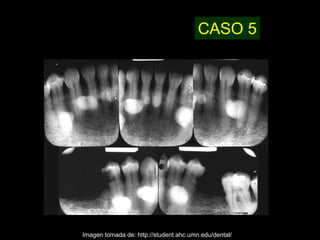

CASO 5

Imagen tomada de: http://student.ahc.umn.edu/dental/

CASO 5 Imagen tomadade: http://student.ahc.umn.edu/dental/